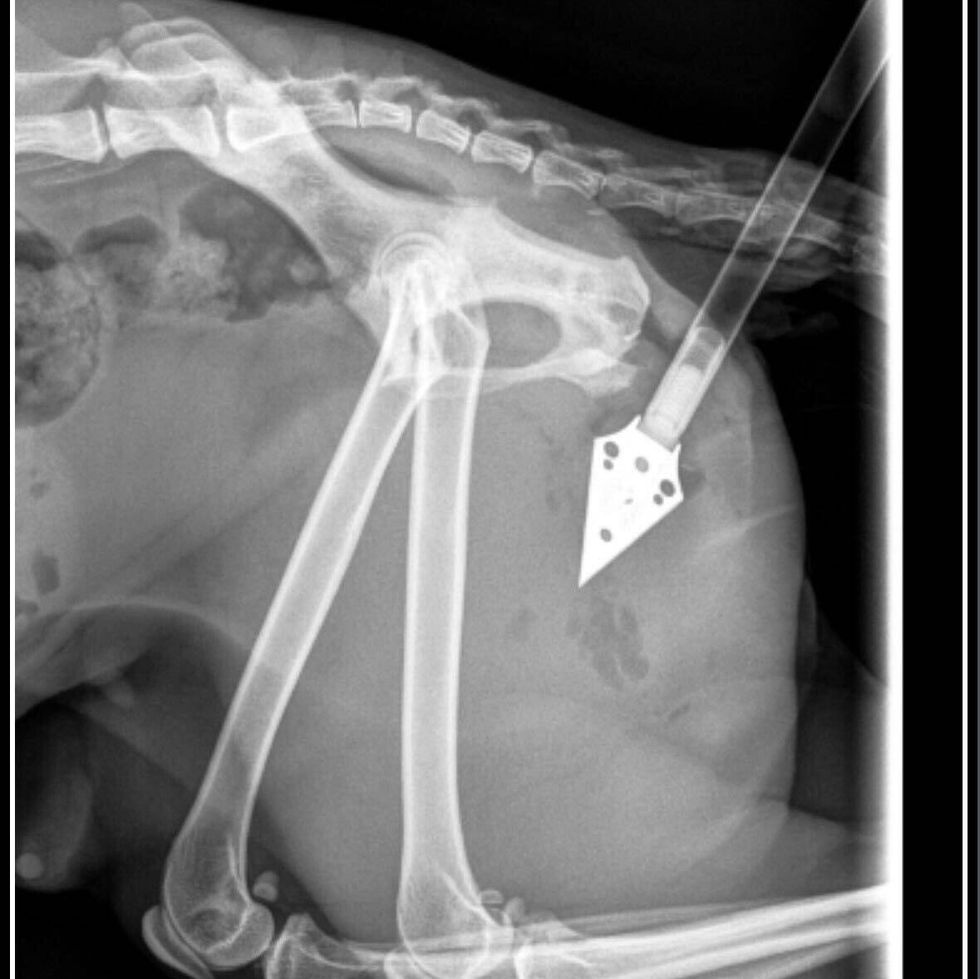

On Thursday, Sept. 19, a caretaker of a cat colony in North Philadelphia went out to feed the animals when, officials say, she discovered one of the cats, Kimiko, had a startling injury: An arrow was sticking out from her right hind leg.

Gillian Kocher, director of public relations at the PSPCA, told KYW the caretaker called animal control, who rushed Kimiko to Philadelphia Animal Specialty and Emergency (PASE), where she was stabilized. She was then taken to PSPCA, where two surgeons removed the arrow and mended her wounds.

"We're lucky that, where the arrow hit — and the cat is lucky, obviously, as well — that it missed all sort of vital parts of her body," said Kocher on Sunday.

"We believe that the arrow came from a crossbow, just based on what it is."